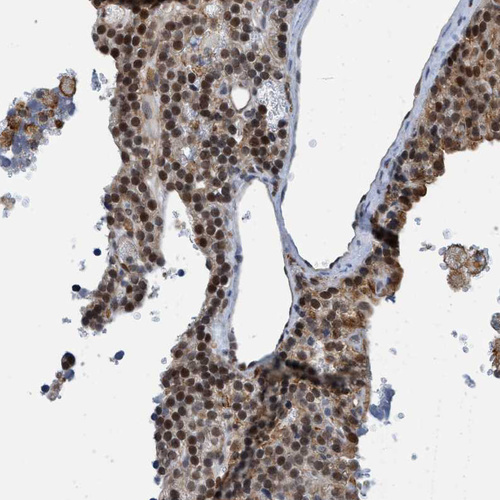

Immunohistochemical staining of human cerebral cortex shows moderate to strong nuclear positivity in neuronal cells.